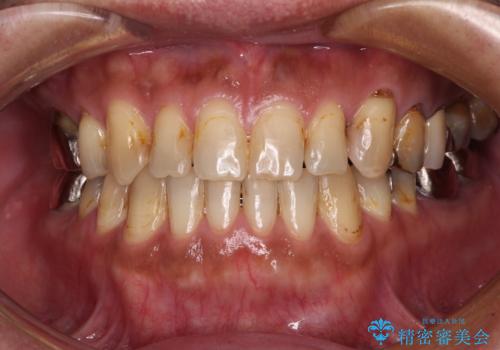

前歯のクロスバイト インビザラインによる矯正治療

- 上下のクロスバイトと前歯のデコボコを気にして来院された患者様です。

インビザラインを用い、IPR(歯と歯の間を削る)と歯列全体を拡大させることで、歯並びを整えていくこととしました。